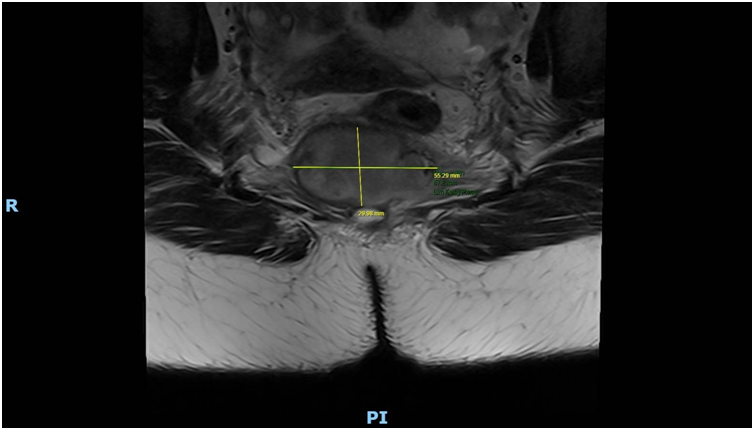

Imaging via MRI and CT demonstrated a complex, encapsulated lesion with peripheral enhancement and restricted diffusion. Multidisciplinary evaluation suggested a congenital epidermoid or duplication cyst. Given the absence of malignancy and surgical complexity, a conservative management strategy was adopted.

Figure 1: Figure 1 Duplication cyst 2025 MRI sagittal plane

Figure 7: Figure 7 Duplication cyst 2025 MRI axial plane